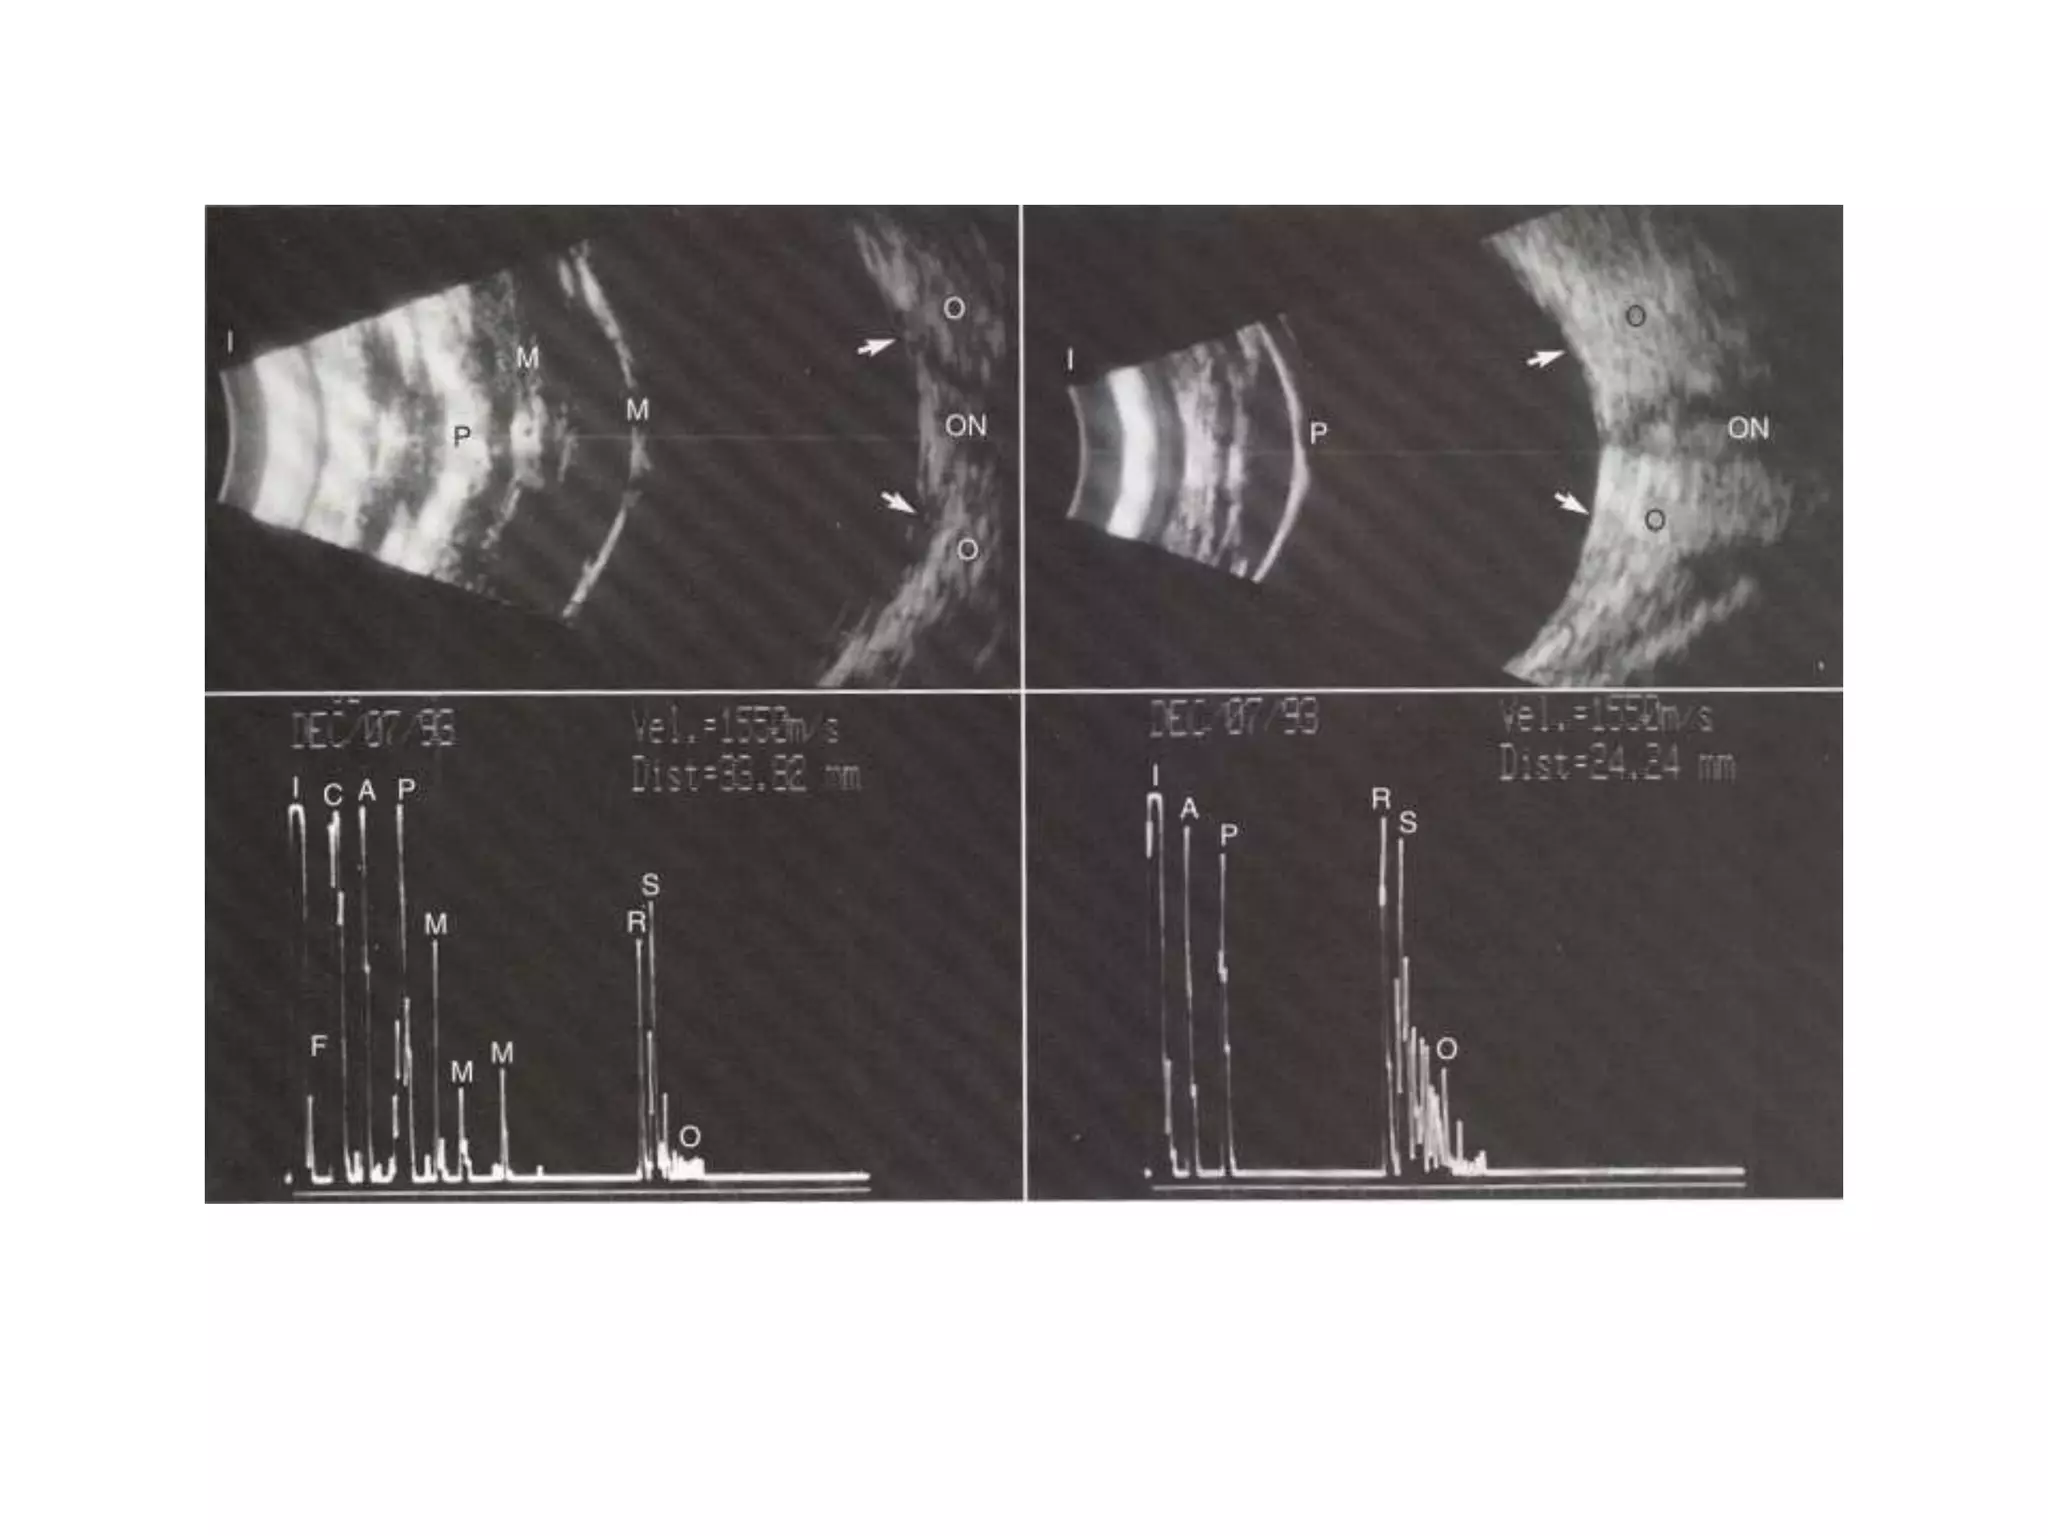

C A P + R S

Posterior Staphyloma

• Posterior staphylomas often causes an irregular shape of the ocular wall

resulting in an inability to display a distinct , high retinal spike , leading to a

significant error in A-scan measurement .

• Deepest portion of the staphyloma may be located eccentric to macula thus the

measurement may be longer than true AL along the visual axis .

• B-scan can be used to demonstrate the shape of posterior ocular wall and the

relationship of macula to the staphyloma .

• Probes with fixation light are preferable